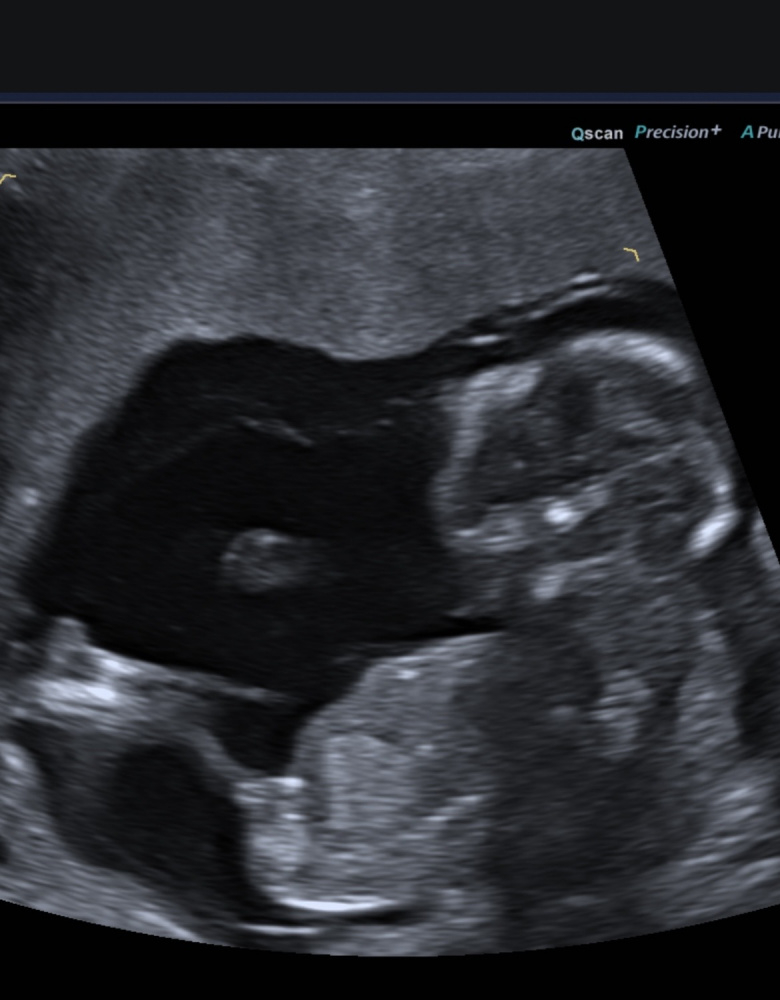

Hallöchen, könnt ihr mir sagen, ob es ein Junge oder Mädchen wird? Ich bin da gerade bei 11+2, doch der FA wusste sofort das Geschlecht, aber wollte es noch nicht sagen…

Also ich kann den Nub leider nicht wirklich erkennen. Hast du vielleicht noch 1-2 andere Bilder?

@Viennagirl87 Also wenn ich den Nub richtig identifiziert habe, dann würde ich auf Mädchen tippen.

Laut Nub Theorie (Bild ist aus der 13. Woche) was denkt ihr? Ist es Team 💕 oder 🩵?

Kann man hier mit der Nub Theorie was erkennen? Ssw 12+5